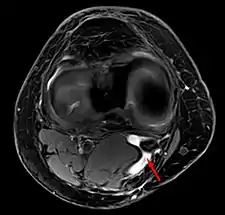

Baker's cyst on axial MRI with communicating channel between the semimembranosus muscle and the medial head of the gastrocnemius muscle.